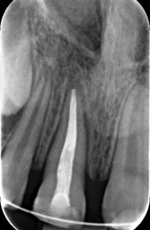

W celu replantacji ząb przemyto jałowym roztworem soli fizjologicznej. Za pomocą gazy korzeń oczyszczono z resztek ozębnej. Następnie umieszczono w żelu Elmex na 20 minut, aby spowolnić ewentualną następową resorpcję (ryc. 2).[3] Kanał został opracowany i wypełniony metodą kondensacji bocznej gutaperki oraz pastą AH PLUS poza jamą ustną. (ryc. 3). Po leczeniu endodontycznym ząb zabezpieczono materiałem Ketac-Fil. Wierzchołek korzenia nieco wygładzono. W znieczuleniu nasiękowym preparatem 4-proc. Ubistesin forte zębodół zbadano i przepłukano solą fizjologiczną. Ząb replantowano z delikatnym naciskiem, zwracając uwagę na zachowanie prawidłowych kontaktów zwarciowych (ryc. 4). Następnie założono ligaturę drucianą, włączając do unieruchomienia zęby 53, 12, 21, 22, 63 (ryc. 5). Wykonano kontrolne zdjęcie RTG (ryc. 6). Ze względu na długi okres przebywania zęba poza jamą ustną w niekorzystnym środowisku oraz wakacyjny wyjazd pacjentki, unieruchomienie pozostawiono na pięć tygodni.